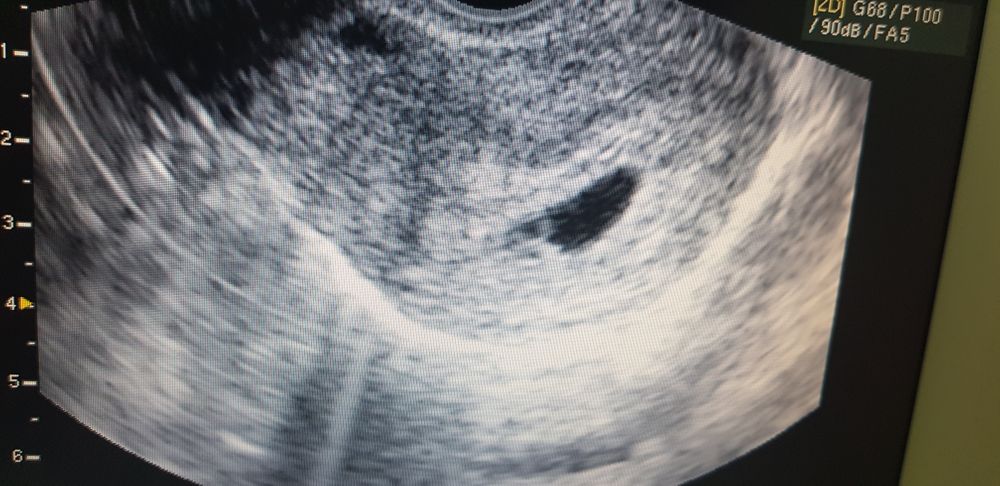

Ну вот! До последнего думала что это меня не коснётся. 10 дек, увидела коричневатую мазню на белье, но решила если повториться утром тогда обращусь к врачам, на утро все хорошо, а к вечеру начал тянуть живот, и покалывало справа возле тазовой кости, кишечник подумала я, а сегодня утром снова мазня но чуть потемнее. Вызвала скорую, сначала сказали на пару дней кладут, а потом по УЗИ увидели отслойку и гематому. Вобщем задержусь я тут дней на 7-10. Зато увидели малыша и подтвердили сердцебиение, хотя послушать не дали